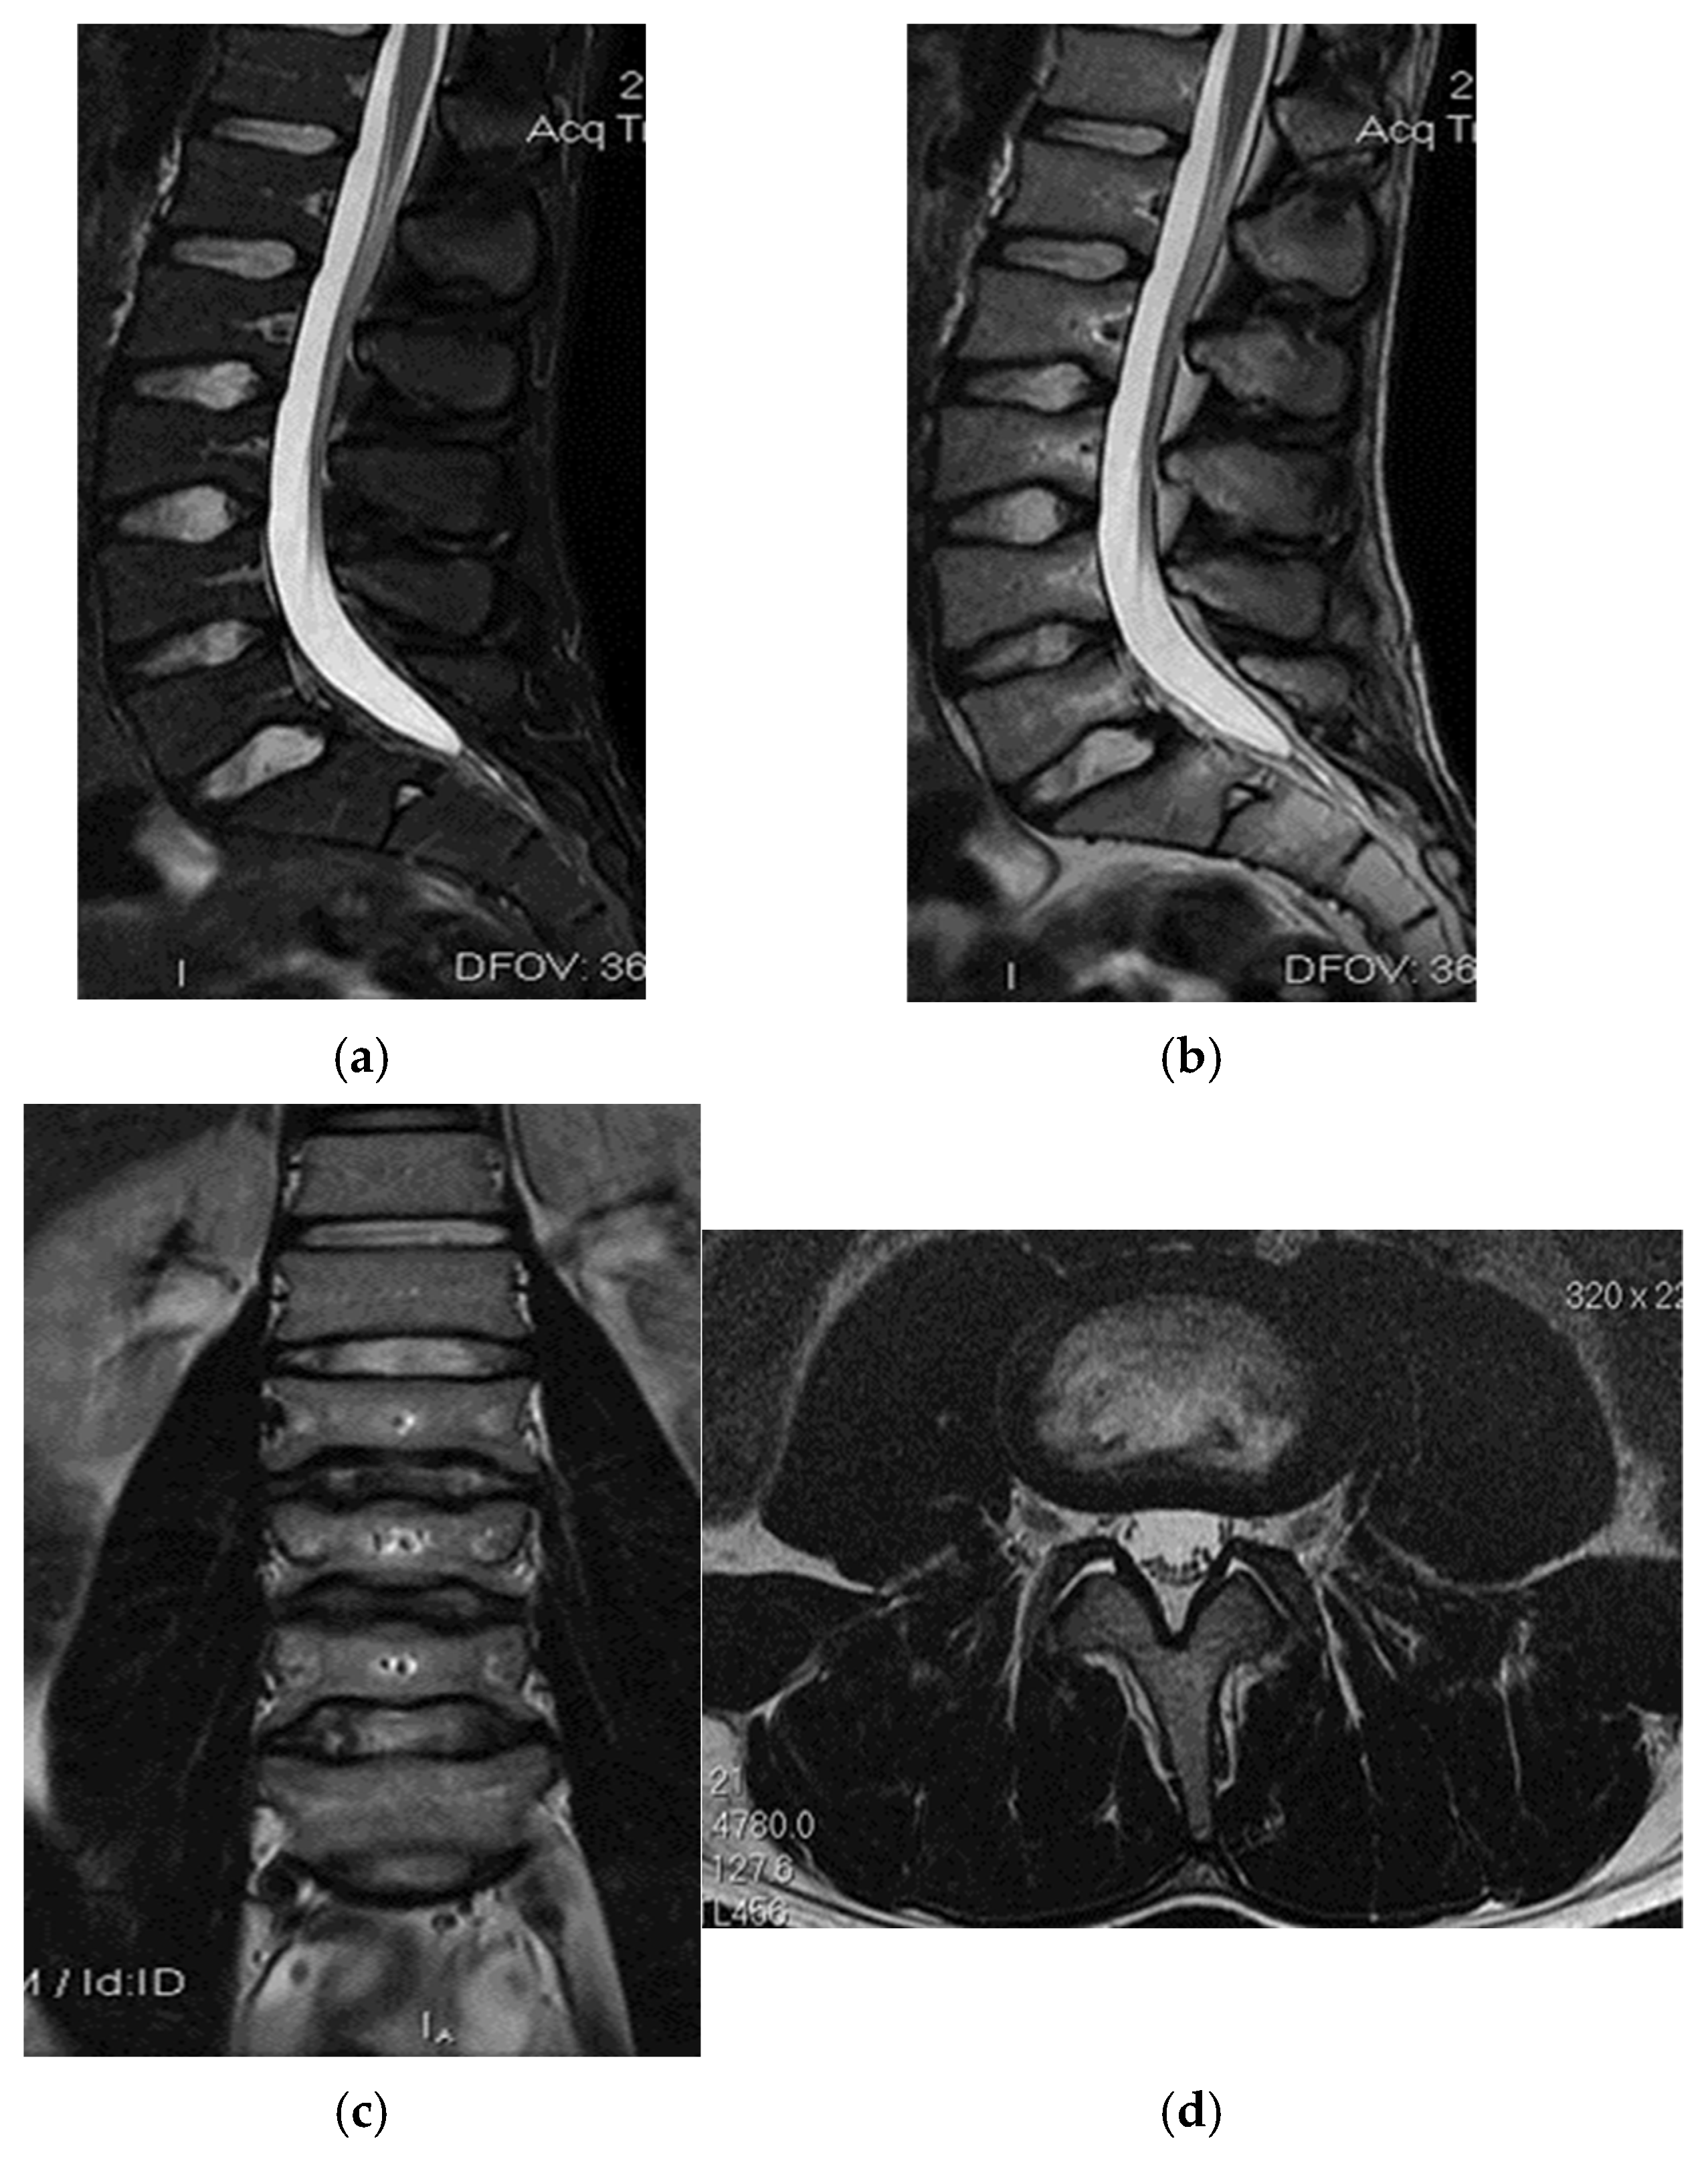

3.1. Case 1: Vastus Lateralis Tear with Prepatellar Hematoma

The spinal MRI revealed no evidence of degenerative lumbar disc pathology or radiculopathy (Figure 5). Magnetic resonance imaging (MRI) and radiographic examination of the pelvis revealed an old avulsion injury with a detached bone fragment at the insertion site on the left ischial tuberosity, involving the semitendinosus, semimembranosus, and biceps femoris muscles (collectively referred to as the ischium-calf muscles). This condition has led to the development of pseudoarthrosis and bone edema at the level of the ischial tuberosity. The sciatic nerve is positioned tangentially to the inflammatory response. Despite the detachment, the bone fragment remains vascularized due to the maintained insertion of the ischial calf muscles, preventing it from becoming a bone splinter (Figure 6 and Figure 7).

Figure 5.

(a) Spinal MRI: sagittal T2 fat sat acquisition, (b) spinal MRI: sagittal T2 acquisition, (c) spinal MRI: coronal T2 acquisition, (d) spinal MRI: axial T2 acquisition.